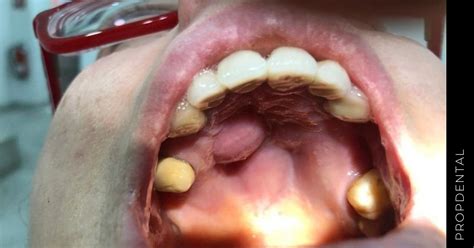

- Torus palatino: El torus palatino es una protuberancia ósea de apariencia dura. Suele tener una causa genética, es asintomático y no duele. Esta alteración suele afectar más a mujeres que a hombres y sus causas son principalmente hereditarias. El torus palatino es una afección poco frecuente, que se explica por la formación de un bulto de hueso en el paladar. La genética suele estar detrás de este tipo de afecciones. Es una anomalía de tipo genético que produce el crecimiento de un bulto benigno que se forma en el paladar y no presenta síntomas durante su aparición.

- Abscesos: Un absceso es un pequeño bulto o inflamación que se localiza cerca de algún diente. A consecuencia de alguna infección los quistes odontogénicos pueden ser frecuentes. Si el bulto en el paladar se ubica muy cerca de algún diente, es muy probable que se trate de un absceso dental.